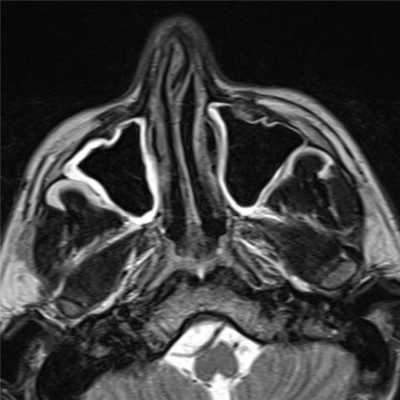

Злокачественные новообразования околоносовых пазух обладают рядом рентгенологических и магнитно-резонансных особенностей, присущих как самому опухолевому очагу, так и окружающим тканям. МР-исследование отличается сигнальными характеристиками тени опухоли, позволяющими судить о природе процесса. Каждый из симптомов необходимо рассматривать в совокупности с другими и с учетом клинических проявлений заболевания, поскольку изучаемый отдельно, он может давать неспецифичную для новообразования картину. Более важная роль в выявлении отличительных признаков злокачественных опухолей принадлежит КТ и МРТ. Только с помощью этих методов удается своевременно определить внутриполостное развитие опухоли, выявить начальные признаки разрушения любой из костных стенок пазух и особенности получения изображения мягкотканной опухоли в зависимости от характера процесса, его природы, что было невозможно ранее при использовании традиционных рентгенологических методик.

- КТ и МРТ являются взаимно дополняющими методами диагностики опухолей полости носа и околоносовых пазух. КТ является методом выбора для оценки костных структур, наличия обызвествления, но возможности ее ограничены при дифференциальной диагностике опухоли от мягких тканей и реактивных изменений в пазухах. Внутривенное введение контрастного йодсодержащего препарата повышает диагностические возможности КТ. Опухолевые массы неравномерно накапливают контрастный препарат, и визуализация их улучшается на фоне реактивного экссудата.

- При МРТ лучше дифференцируется опухоль, реактивный выпот и отек слизистой, что позволяет более точно определить размеры опухоли и ее распространенность. Применение внутривенного усиления при КТ и МРТ улучшает оценку размеров, визуализацию структуры и границ опухоли, а также размеров внутричерепного компонента.

- МРТ - высокоинформативный дифференциально-диагностический метод в диагностике рака околоносовых пазух и полости носа, отличающийся высокой естественной тканевой контрастностью изображения, отсутствием лучевой нагрузки и получением многоплоскостных срезов, высокой чувствительностью (96,5%) и специфичностью (70,8%) в выявлении опухолевой и воспалительной патологии околоносовых пазух.

- При злокачественных новообразованиях околоносовых пазух МРТ-изображение характеризуется неоднородной структурой и чаще МР-сигналом различной интенсивности, неправильной формой, неровными и прерывистыми контурами, наличием инфильтрации окружающих тканей. При этом сопутствующий опухоли воспалительный экссудат всегда имеет более высокий сигнал интенсивности. Чувствительность МРТ при злокачественных опухолях параназальных синусов составила 91,3%, специфичность - 59,1%. Степень интенсивности МР-сигнала и однородности (или неоднородности) его структуры при воспалительных заболеваниях околоносовых пазух зависит от особенностей течения и фазы воспалительного процесса, при этом чувствительность МРТ составила 98,8%, специфичность - 92,3%.